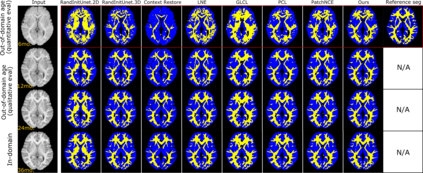

Recent self-supervised advances in medical computer vision exploit global and local anatomical self-similarity for pretraining prior to downstream tasks such as segmentation. However, current methods assume i.i.d. image acquisition, which is invalid in clinical study designs where follow-up longitudinal scans track subject-specific temporal changes. Further, existing self-supervised methods for medically-relevant image-to-image architectures exploit only spatial or temporal self-similarity and only do so via a loss applied at a single image-scale, with naive multi-scale spatiotemporal extensions collapsing to degenerate solutions. To these ends, this paper makes two contributions: (1) It presents a local and multi-scale spatiotemporal representation learning method for image-to-image architectures trained on longitudinal images. It exploits the spatiotemporal self-similarity of learned multi-scale intra-subject features for pretraining and develops several feature-wise regularizations that avoid collapsed identity representations; (2) During finetuning, it proposes a surprisingly simple self-supervised segmentation consistency regularization to exploit intra-subject correlation. Benchmarked in the one-shot segmentation setting, the proposed framework outperforms both well-tuned randomly-initialized baselines and current self-supervised techniques designed for both i.i.d. and longitudinal datasets. These improvements are demonstrated across both longitudinal neurodegenerative adult MRI and developing infant brain MRI and yield both higher performance and longitudinal consistency.